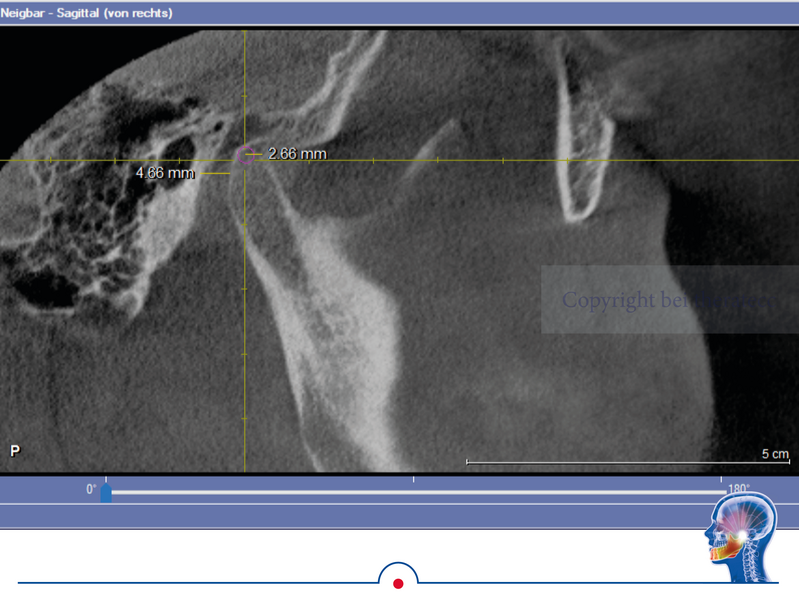

Grundsätzlich ist es logisch, dass die habituelle Okklusion den Patienten in

seine jeweilige Kondylenposition „zwingt“. Das kann man sehr schön bei einer

DVT-Aufnahme erkennen, wenn diese ohne frontalen Aufbiss in habitueller Okklusion realisiert wird.

In dem DVT wird sichtbar, dass der linke Kondylus in habitueller Bisslage um

ca. 2,5 mm deutlich zu anterior positioniert ist. Ursache dafür ist der Zahnkontakt bei 26 und 36. Dieser Zahnkontakt zwingt den Unterkiefer linksseitig in die anteriore Kondylenposition. Wenn jetzt in diesem Gebiss eine klassische Handbissnahme für eine Zahnversorgung durchgeführt wird, wird diese „falsche Kondylenposition“ in den Artikulator übertragen.

In dem hier vorgestellten Fall wurden diese Parameter zusätzlich im DVT bestimmt. Die im DVT ermittelte sagitale Gelenkbahnneigung beträgt rechts 41,9° und links 38,3°. Die mit Centric Guide® 3D ermittelte Gelenkbahnneigung beträgt rechts 43,86° und links 38,03°. Damit weichen die beiden Werte rechts nur um 1,96° und links nur um 0,27° voneinander ab. Wenn man sich die Gelenkbahneinstellung im Vollwertartikulator anschaut, stellt man schnell fest, dass diese nur in 5° Schritten erfolgt.